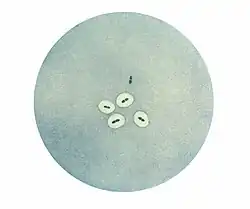

Photomicrograph of Streptococcus pneumoniae bacteria revealing capsular swelling using the Neufeld quellung test. Notice the two streptococci at the top of the photo that appear to have no capsule.

The quellung reaction, also called the Neufeld reaction, is a biochemical reaction in which antibodies bind to the bacterial capsule of Streptococcus pneumoniae, Klebsiella pneumoniae, Neisseria meningitidis, Bacillus anthracis, Haemophilus influenzae,[1] Escherichia coli, and Salmonella. The antibody reaction allows these species to be visualized under a microscope. If the reaction is positive, the capsule becomes opaque and appears to enlarge.

Quellung is the German word for "swelling" and describes the microscopic appearance of pneumococcal or other bacterial capsules after their polysaccharide antigen has combined with a specific antibody. The antibody usually comes from serum taken from an immunized laboratory animal. As a result of this combination, and precipitation of the large, complex molecule formed, the capsule appears to swell, because of increased surface tension, and its outlines become demarcated.